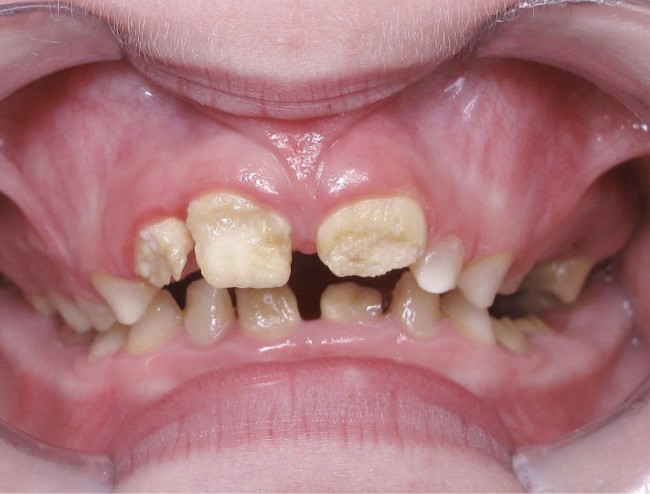

Il existe des anomalies dentaires (tabl. I) [1-12], mais aussi occlusales associées aux AI (fig. 1 et 2).

Selon de nombreuses études, l’anomalie occlusale la plus fréquemment retrouvée en association avec les AI est l’infraclusion antérieure, puisqu’elle est retrouvée chez 22 à 64 % des patients présentant cette affection, et encore plus chez les femmes [2,8,13-19]. Cette anomalie touche tous les types d’AI mais à des degrés très divers. Son incidence semble élevée dans les formes hypominéralisées, moindre dans les formes hypoplasiques et nettement moindre dans les formes hypomatures [8,17,18]. La sévérité de l’atteinte amélaire ne semble pas corrélée avec la présence ou l’intensité de cette malocclusion [17].